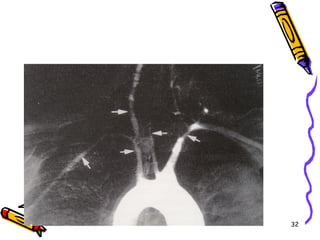

TAKAYASU ARTERİTİ

•   Kadınlarda

•   40 yaşından önce

•   Asya ülkelerinde

•   Klasik olarak aortik ark tutulumu

•   1/3 vakada aortun diğer kısımları ve

pulmoner arter

Klinik gidiş

• Üst ekstremite nabızlarında

zayıflama

• Görme bozukluğu

• Nörolojik defisitler

• Ht

– Ölüm en sık KKY ve MI nedeniyledir

Mikroskobi

• Erken dönemde vazovazorumda

perivasküler iltihabi hücre birikimi ve

adventisiada MNH infiltrasyonu

• Daha sonraki dönemde mediada

mononükleer infiltrasyon ve bazan

granülomatöz reaksiyon